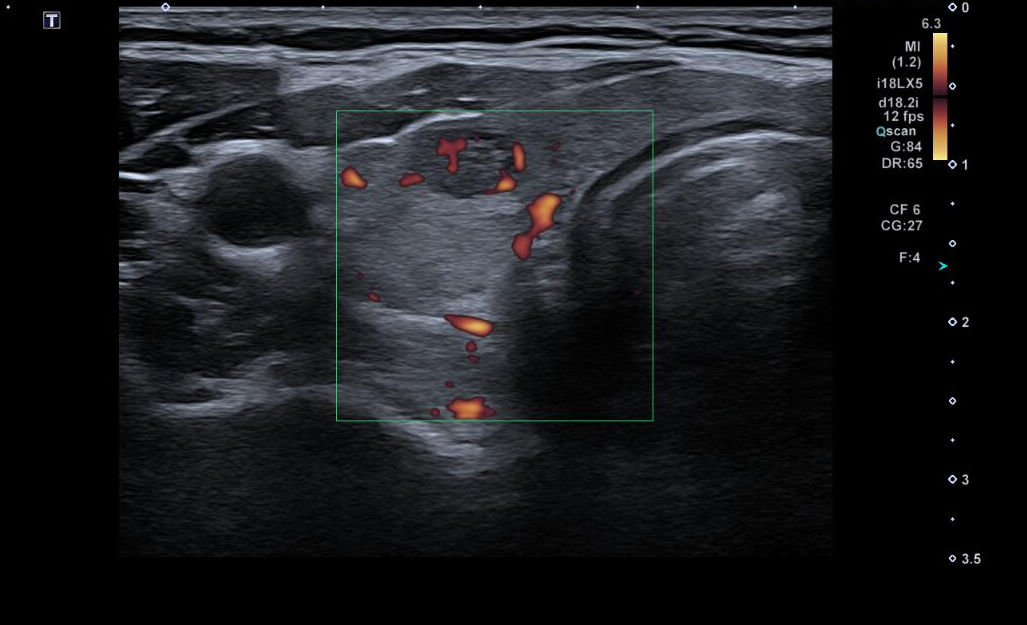

Tras dichos hallazgos, se decide realización de Ecografía Clínica.

Ecografía clínica:

Ecografía reglada (Servicio de Radiología):

Tiroiditis autoinmune hipertiroidea.

Tras la realización de Ecografía Clínica y Ecografía Reglada, junto con las pruebas inmunológicas, se realiza diagnóstico de tiroiditis autoinmune, no siendo necesaria la realización de pruebas diagnósticas adicionales. Seguimiento de función tiroidea en 3 meses y evolución de la clínica.